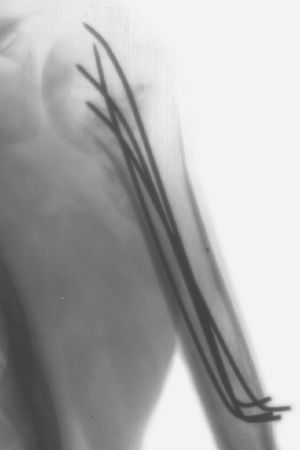

Intraoperative X-ray of a Humerus fixated by Kirschner wires